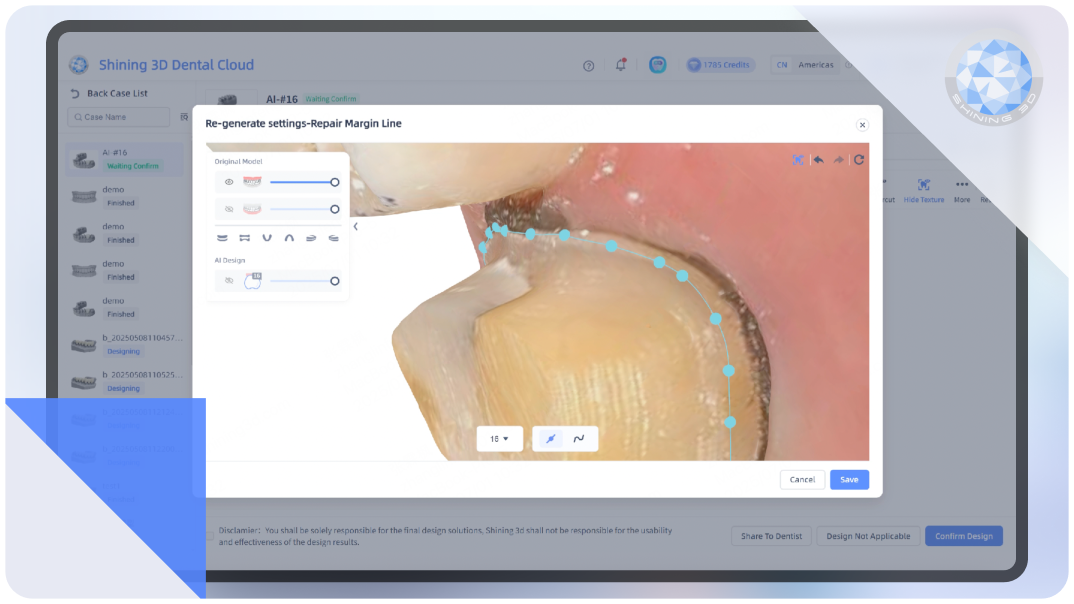

AI Crown

Intelligently generates dental crowns, auto-filling undercuts with meticulous precision.